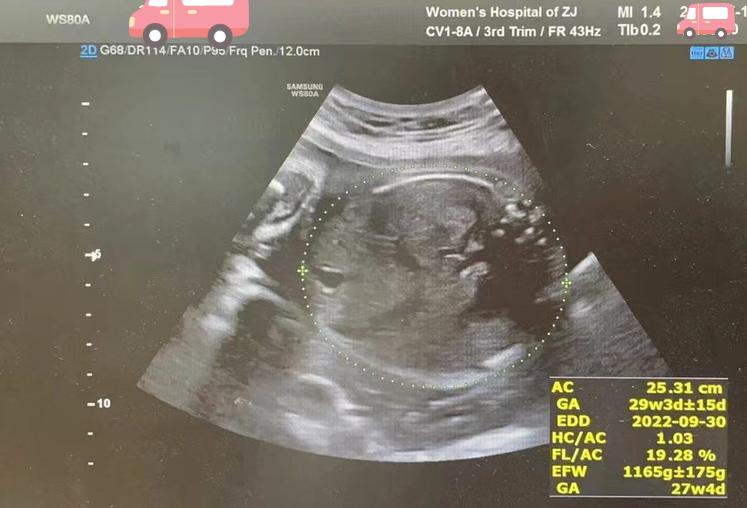

每周都给产妇做一次超声,评估B胎儿的生长状况和宫颈长度。

B胎分娩前B超图像

妊娠28周

妊娠28周妹妹平安降生,1270g,新生儿评分1分钟、5分钟分别为9分和10分,随后转至新生儿重症监护室治疗,没有出现严重的早产儿并发症,体重也稳步增长达到2440g,一个月后平安回家。